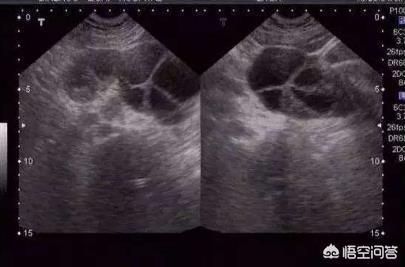

2)在测定排卵数目以及成熟度方面优势明显,对于切除一侧输卵管的女性(尤其是有过“宫外孕”史的)还能够准确测出是哪个卵巢排卵,是否有优势卵泡排出也能直观看到;

3)准确测定卵泡大小以及子宫内膜的厚度;

我们在进行卵泡监测的同时,监测的标准是确认女性排卵或者是认定女性卵泡发育不良、卵泡黄素化为止。我们不能一看到优势卵泡或成熟卵泡就立马停止监测。这里面大家有个点需要注意,就是我们会在临床中看到有些发育不良的优势卵泡可能会逐渐萎缩变小。特别是排卵障碍中,有些卵泡可以长到30--40mm甚至更大,并且出现黄素化。

这个时候B超监测就会出现卵泡内出现网状絮状回声及强光点。